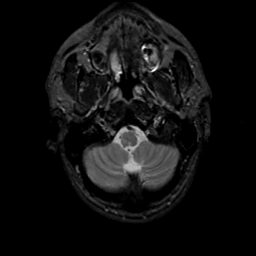

MR Study #16, June 23, 1991 -- Slice #5